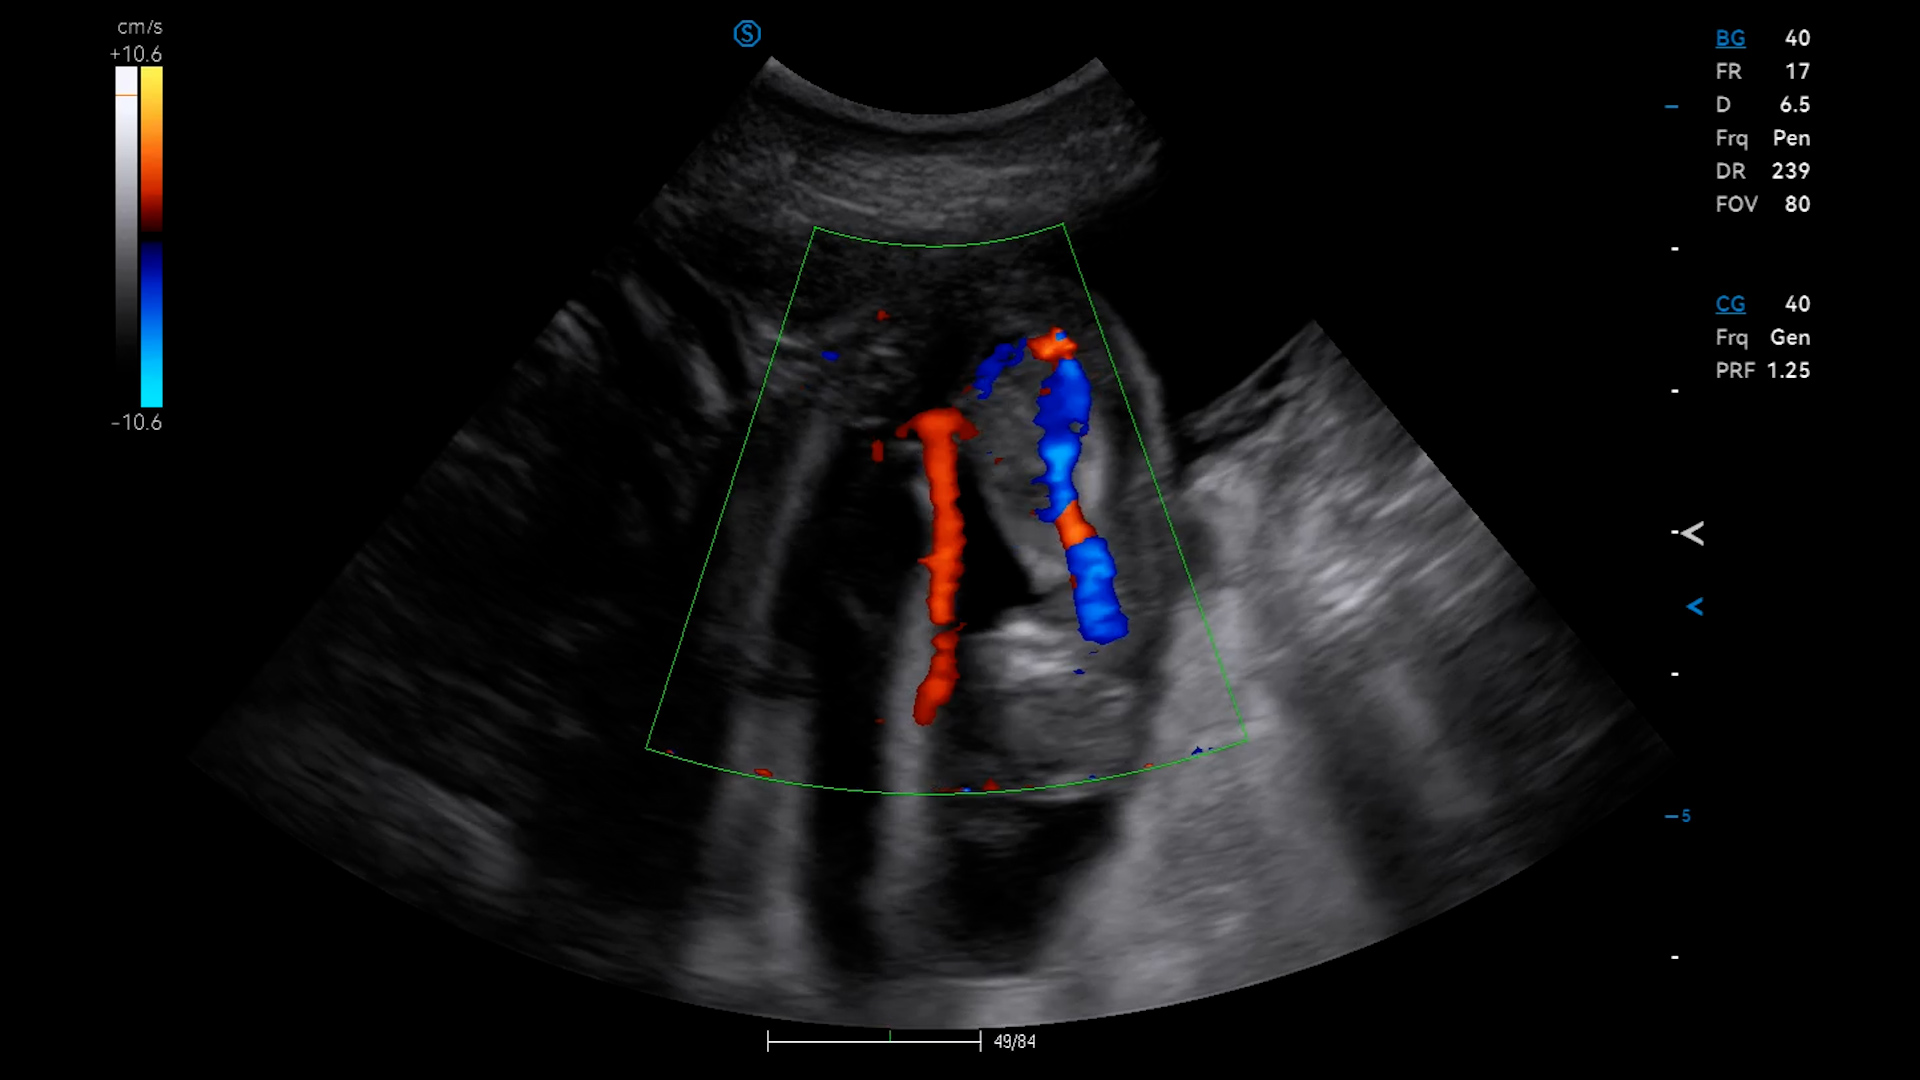

Seven the Frenchie came today for her first pregnancy scan, here at our ultrasound lab in Bromley. We saw between 5-7 very active pups (but wouldn’t 7 just be perfect!).